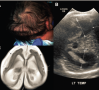

Título:  La microcefalia congénita: un reto diagnóstico durante las epidemias de Zika

Descripción: La reciente epidemia del virus Zika (ZIKV) en América Latina ha puesto de relieve la necesidad de una mejor comprensión de los mecanismos patológicos subyacentes de la microcefalia, que incluyen tanto causas infecciosas como no infecciosas. El enfoque diagnóstico de la microcefalia debe incluir posibles etiologías infecciosas y genéticas, así como exposiciones ambientales en el útero, como alcohol, toxinas y medicamentos.